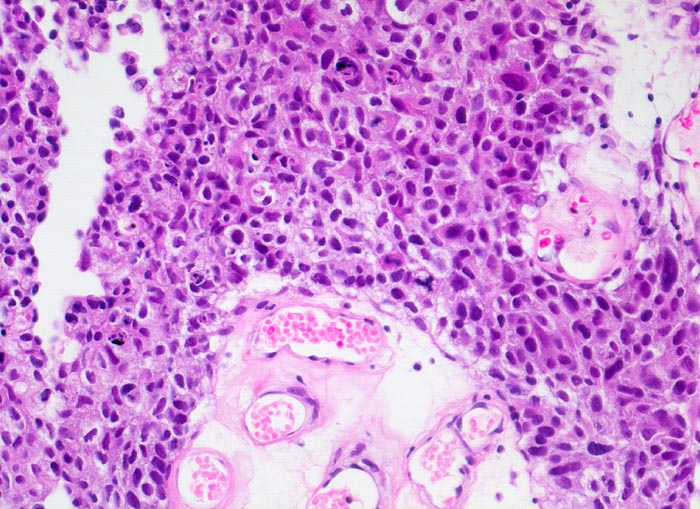

Urothelkarzinom G3

maligner Tumor

Sediment von Urin und Harnblasenspülflüssigkeit sind oft zellreich. Die meist einzeln liegenden Tumorzellen sind deutlich grösser als Parabasalzellen und Basalzellen. Die Atypien sind meist auf den ersten Blick zu sehen. Die deutlich vergrösserten Kerne sind hyperchromatisch und sehr grob strukturiert. Sie können den lavabrockenartigen Kernen von Plattenepithelkarzinomen ähneln. Die Kernpolymorphie ist ausgeprägt. Das Zytoplasma kann Vakuolen und abortives Sekret enthalten. Der Ausstrichhintergrund ist detritisch und blutig.